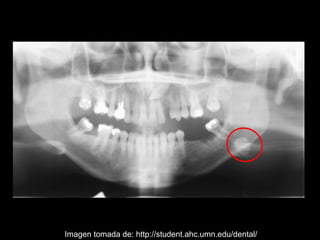

La sialolitiasis es la formación de obstrucciones mineralizadas en las glándulas salivales, causadas por el depósito de calcio y fósforo. Puede presentarse en las glándulas salivales mayores y menores, causando inflamación e hinchazón e incluso dolor durante las comidas. Los sialolitos se ven en radiografías como densidades radiopacas de varias formas y tamaños dentro de los conductos glandulares. El diagnóstico diferencial incluye otras imágenes radiopacas en los tejidos blandos.